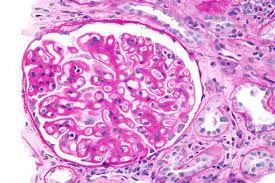

Injúria Renal Aguda (revisão Lancet 2025)